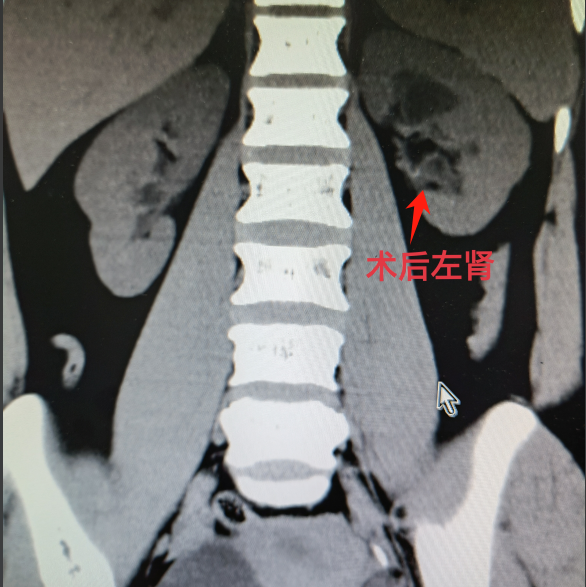

术后左肾结石清理干净